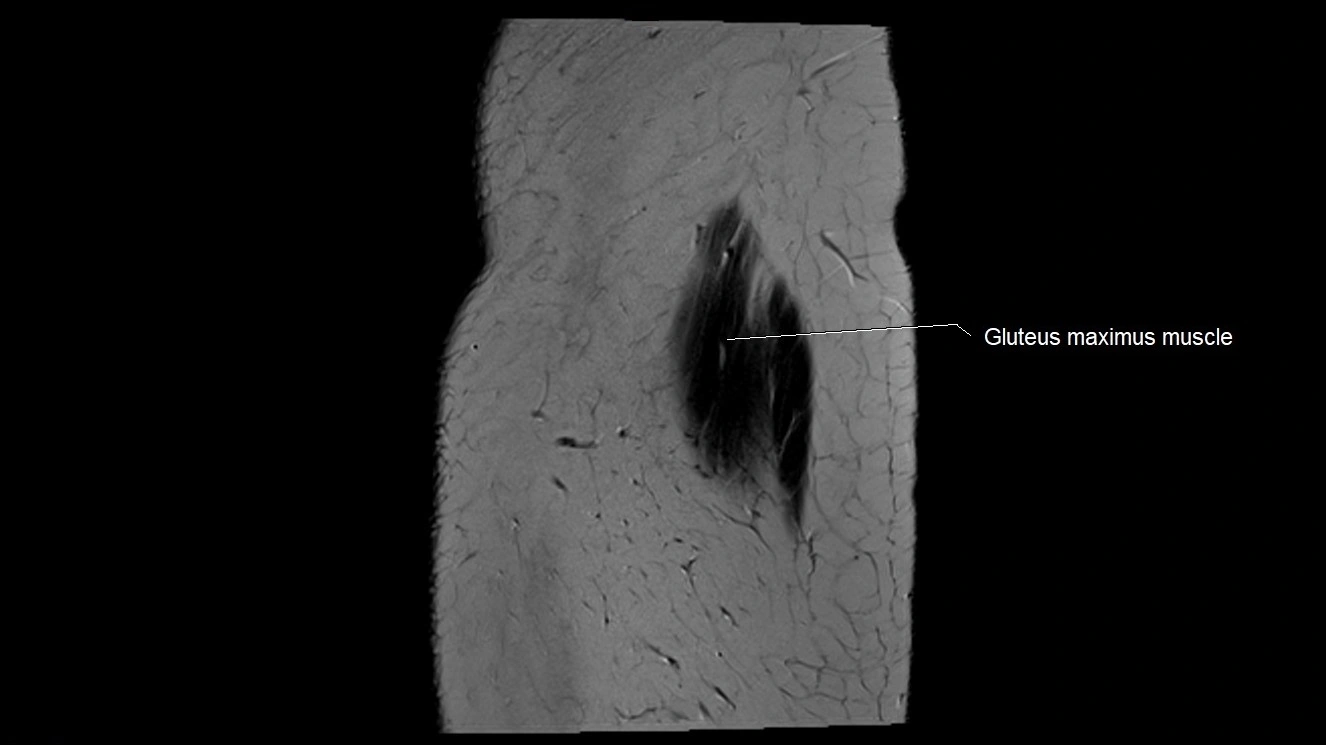

- Gluteus maximus muscle